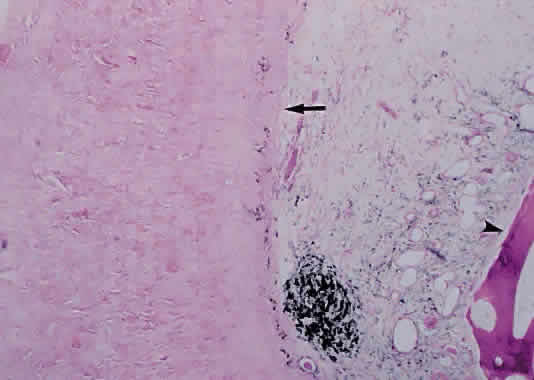

PROGRESSIVE OUTER RETINAL NECROSIS. Descriptively named, progressive outer retinal necrosis is a progressive, multifocal, necrotizing inflammation of the outer retina. Unlike CMV retinitis, it is not associated with significant retinal vasculitis. Caused by the varicella zoster virus, it often follows an episode of cutaneous zoster.108 Rutzen and associates109 reported the histopathology from two cases of progressive outer retinal necrosis requiring retinal biopsy. Retinal necrosis was present in one, with the other showing only retinal atrophy (Fig. 12). Both revealed herpes group viral DNA. Unlike the typical occlusive vasculitis seen in CMV retinitis, retinal vessels were patent in the case with retinal necrosis.

Fig. 12. Photomicrograph of retina from a patient with progressive outer retinal necrosis showing loss of normal retina architecture but preservation of retinal vessels (arrow) (hematoxylin and eosin; × 200).